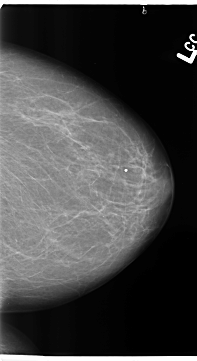

B_3140_1.LEFT_CC

LEFT_CC LINES 4688 PIXELS_PER_LINE 2552 BITS_PER_PIXEL 12 RESOLUTION 50 NON_OVERLAY